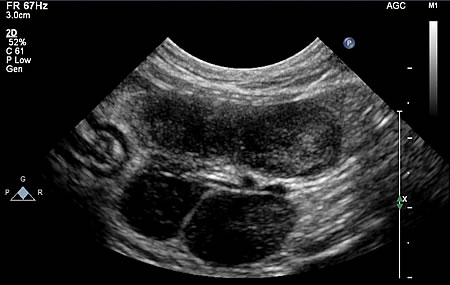

子宮蓄膿症

中齢から高齢の不妊手術をしていない雌猫がかかる疾患で、子宮内に膿がたまることで起こります。外陰部から血様や膿状の排泄物が認められて気づいたり、子宮が拡張し、お腹がふくらむことで気づくこともあります。

内部に大量の膿が貯留し、拡張した子宮